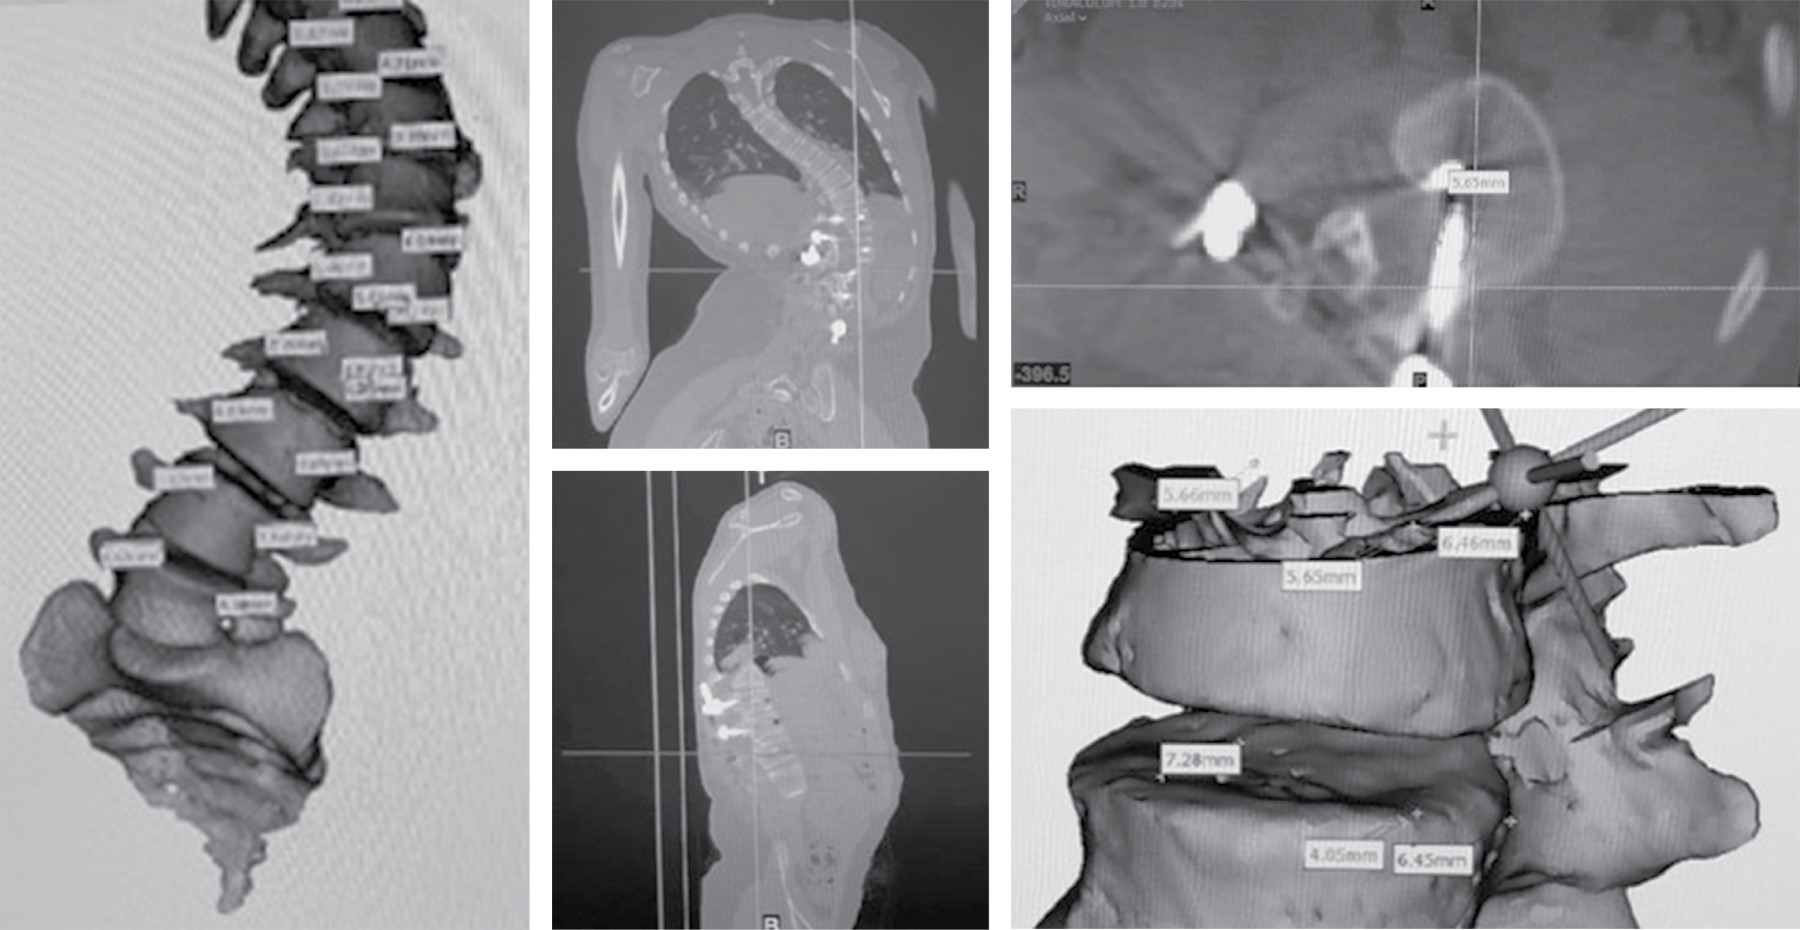

Introduction: Scoliosis is a complex deformity that affects all three planes of the axis of the spine. The association between neuromuscular pathology and vertebral alignment was initially described in 1960. Neuromuscular pathology is progressive and results in postural abnormalities. Surgical goals in patients with neuromuscular deformity include anatomical correction for sedation and ambulation, as well as functional improvement. The gold standard of treatment is by posterior approach with transpedicular screws. The "hands-free" technique saves surgical time, decreases radiation by reducing the use of fluoroscopy. The advent of 3D printing technology allows precise study of the anatomical area and detail of the deformity in its three planes. This model can be sterilized for transoperative guidance. A 13-year-old female patient who develops thoracolumbar neuromuscular scoliosis secondary to spastic cerebral palsy (CP), with previous instrumentation T11-L3 of which he develops severe proximal curve. After the segmentation of the three-dimensional model, pedicle violation greater than 2 mm towards bilateral medullary canal was detected in the pedicles of L1 and L2 of previous instrumentation, pedicle dysplasia and the morphological characteristics of the pedicles were observed. Three-dimensional planning and the use of surgical guides represent a tool for surgical planning, especially in severe cases and with pedicle dysplasia. It helps as a surgical guide for the placement of hands-free transpedicular screws with possible reduction of radiation and anesthetic time.

Figure 7

2020     |     www.medigraphic.com